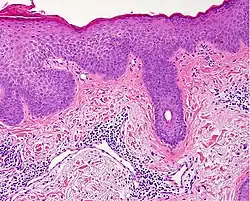

Interface dermatitis with lichenoid inflammation

| Generally/Not otherwise specified | Typical findings:[2]

|

| Lichen planus | Irregular epidermal hyperplasia with a jagged “sawtooth” appearance, compact hyperkeratosis or orthokeratosis, foci of wedge-shaped hypergranulosis, basilar vacuolar degeneration, slight spongiosis in the spinous layer, and squamatization. The dermal papillae between the elongated rete ridges are frequently dome shaped. Necrotic keratinocytes can be observed in the basal layer of the epidermis and at the dermal-epidermal junction. Eosinophilic remnants of anucleate apoptotic basal cells may also be found in the dermis and are referred to as “colloid or civatte bodies”. Whickham striae are usually seen in the areas of hypergranulosis. Vacuolar degeneration at the basal layer may be noted leading to focal subepidermal clefts (Max Joseph spaces). Squamatization occurs as a result of maturation and flattening of cells in the basal layer. It happens in areas of marked hypergranulosis with prominence of the sawtooth pattern of rete ridges. Wedge-shaped hypergranulosis can occur in the eccrine ducts (acrosyringia) or hair follicles (acrotrichia). In the hypertrophic subtype, the associated hyperkeratosis, parakeratosis, hypergranulosis, papillomatosis, acanthosis, and hyperplasia markedly increased with thicker collagen bundles forming in the dermis. Moreover, the rete ridges are more elongated and rounded as opposed to the typical sawtooth pattern. In atrophic LP, loss of the rete ridges and dermal fibrosis is prominent. In vesiculobullous LP, the disease progression is quicker. Hence, some of the distinctive features such as hyperkeratosis, hypergranulosis, or dense lymphocytic dermal-epidermal infiltrate may not be present. LP lesion may resolve with residual hyperpigmentation caused by a persistent increase in the number of melanophages in the papillary dermis.[9] | ![]() |